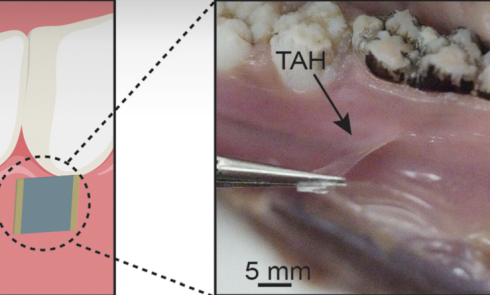

La dysesthésie occlusale (DO) se définit comme une perception anormale et persistante de l’occlusion, générant un inconfort important malgré l’absence...Les matériaux de restauration fibrés dans le traitement de la dent dépulpée : indications et limites

La restauration des dents traitées endodontiquement et délabrées représente un défi majeur en chirurgie dentaire. Leur structure compromise en raison...Les couronnes périphériques : vertiprep versus préparations horizontales